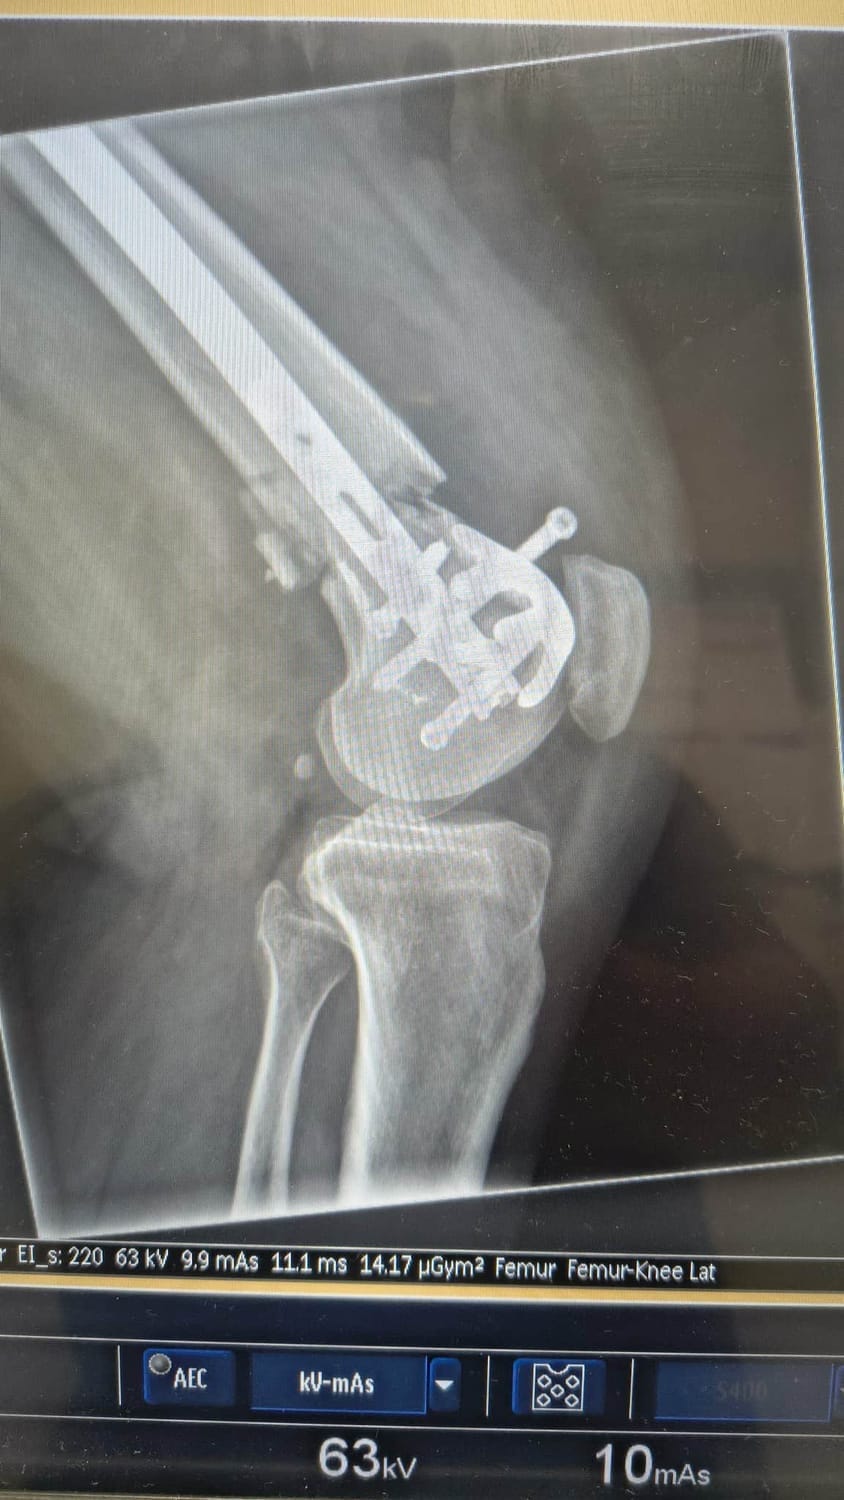

The skilled surgical team had to insert a 12-inch rod through my femur, stretching from near my hip right down to my knee, which was then secured firmly with bolts at each end to stabilize the fracture. Additionally, they had to thoroughly clean and enlarge the wound area where the bone broke through my skin, which left me with a substantial 21 staples in total.